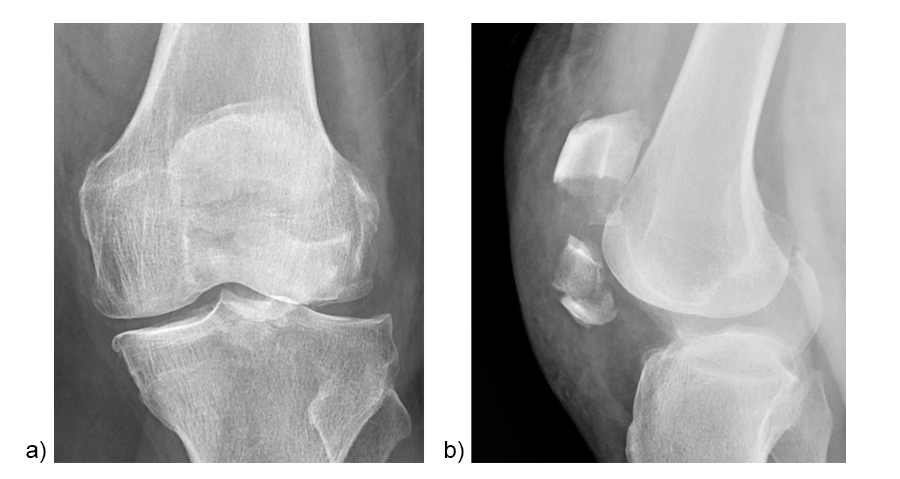

A 71-year-old obese woman with osteoporosis sustained a fall from standing height with a direct blunt trauma on the left knee. It was impossible for her to walk or extend the knee. X-rays revealed a complex patella fracture with a comminuted distal pole (Fig 5).

A CT scan was performed to assess the complexity of the fracture pattern (Fig 6).